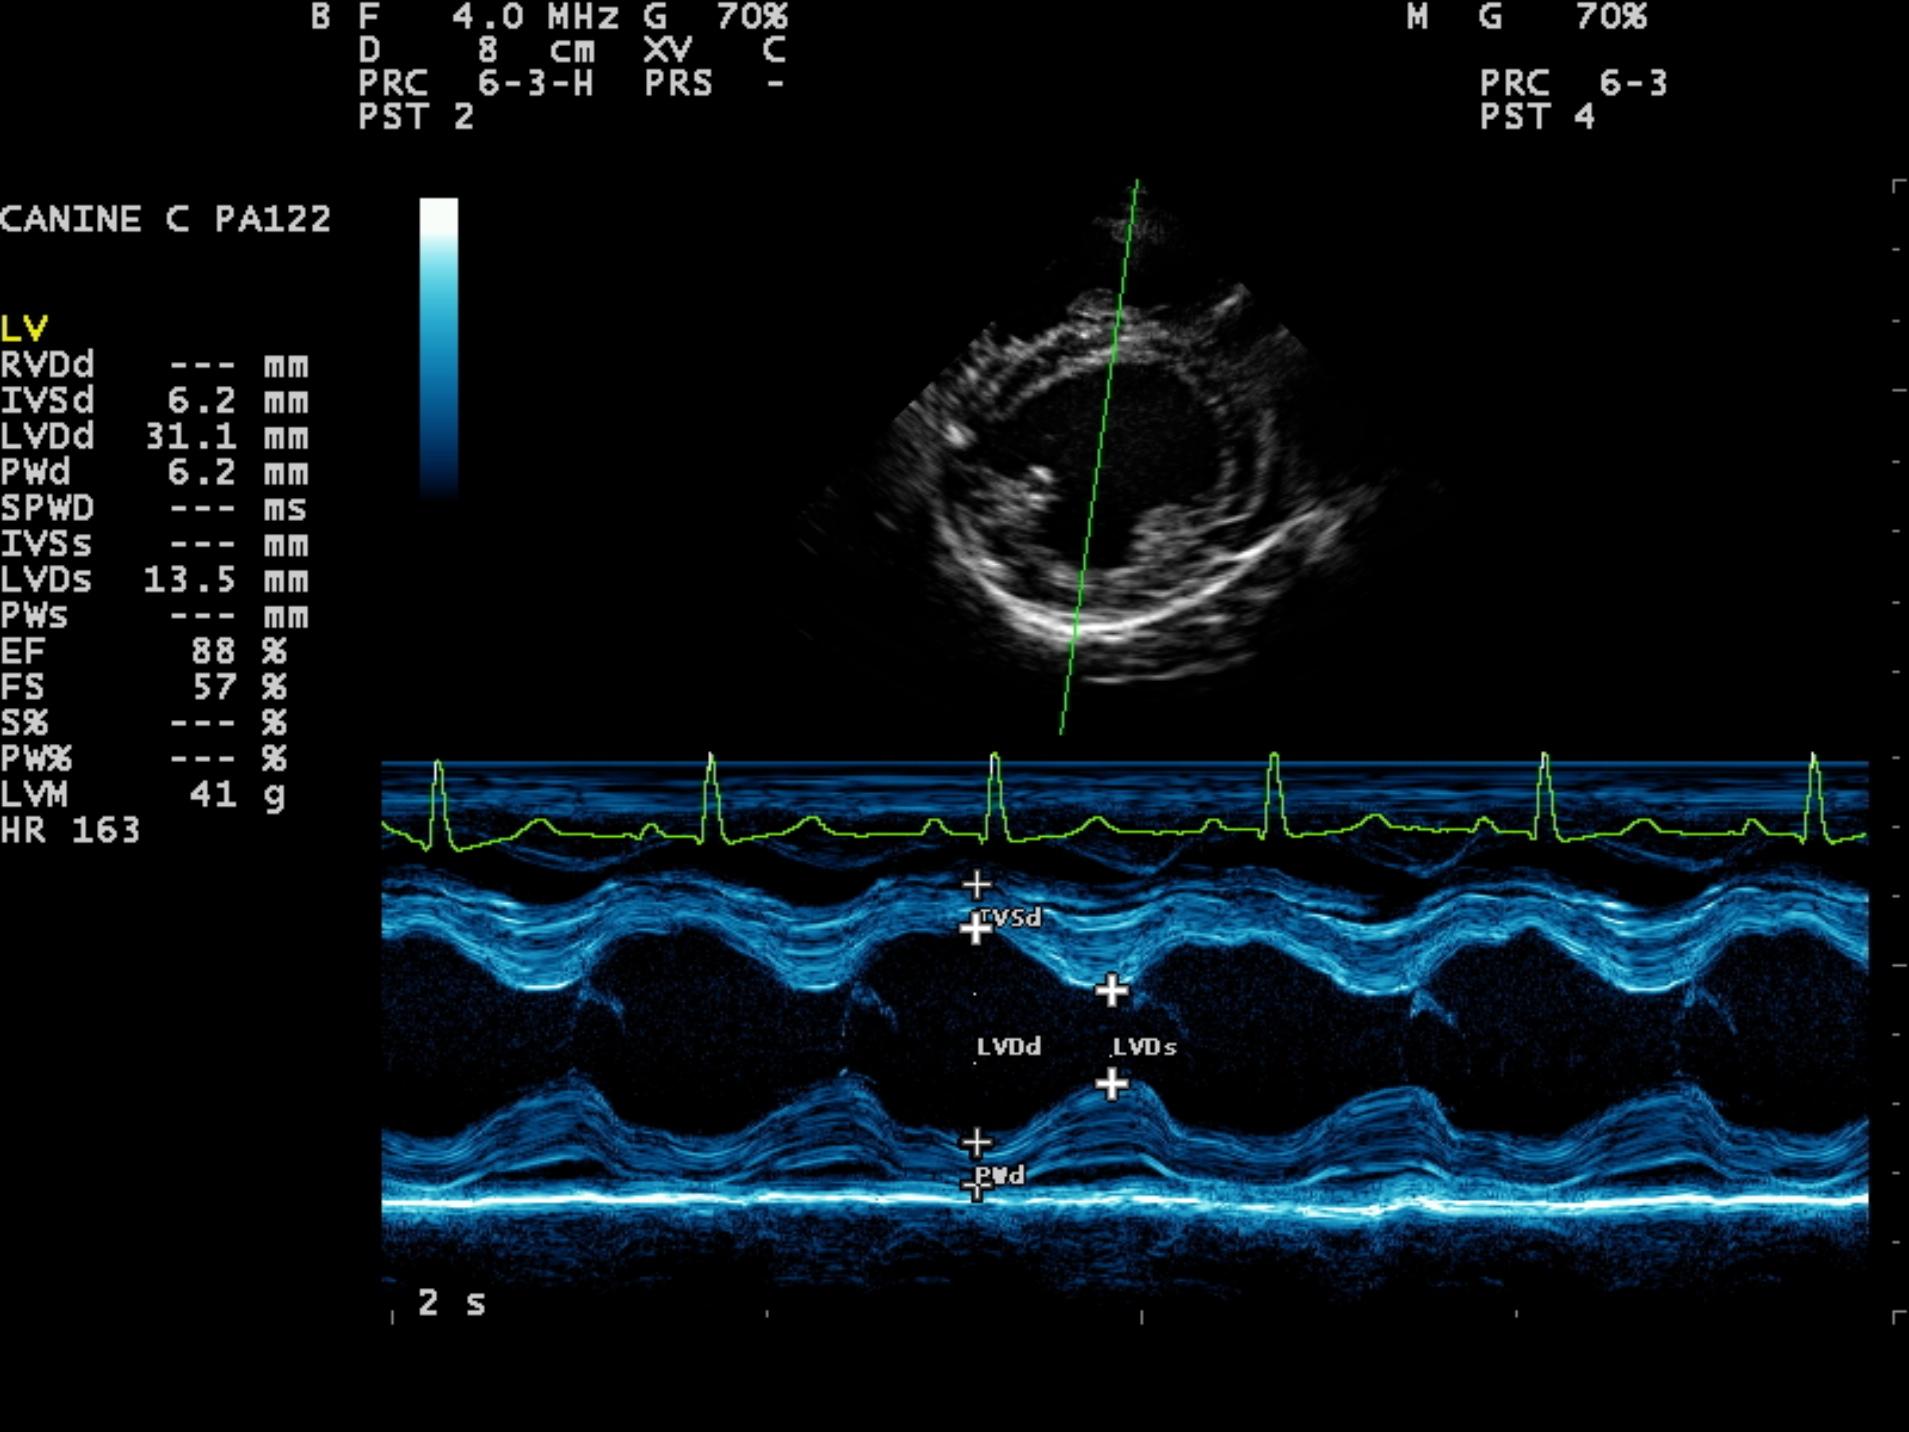

An 8-year-old F Maltese was presented for examination. A grade 5/6 systolic heart murmur was noted. Radiographs revealed severe generalized cardiomegaly and an unremarkable pulmonary parenchyma. Moderate hepatomegaly and ascites was additionally noted.